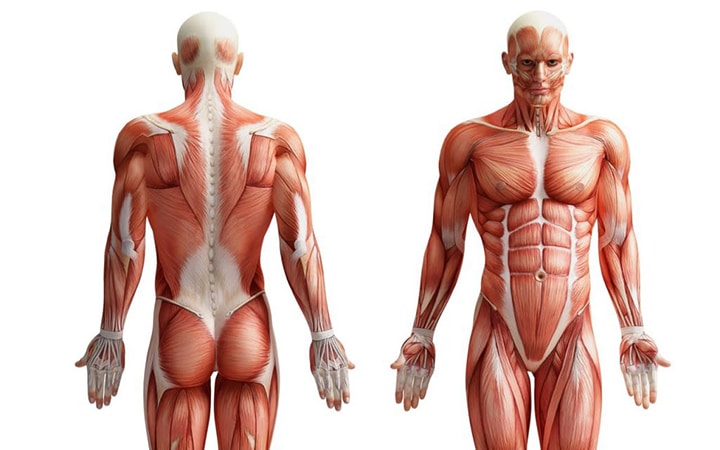

قیمت: 52٬000 تومان - دسته بندی فایل: پاورپوینتپاورپوینت آناتومی بدن انسان

فروش ویژه پاور پوینت حرفه ای بیماری انسدادی مزمن ریه با تخفیف استثنایی فقط 62000 هزار تومان تعداد اسلاید: 26 اسلاید

قیمت: 108٬000 تومان - دسته بندی فایل: پاورپوینتپاورپوینت آشنایی با اناتومی انسان

فروش ویژه پاور پوینت حرفه ای آشنایی با اناتومی انسان ریه با تخفیف استثنایی فقط 124000هزار تومان تعداد اسلاید: 67 اسلاید